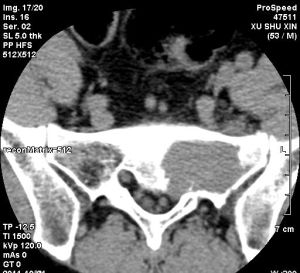

1.影像學技術的發展:包括更清晰的數字X光片、CT、MRI、ECT等技術臨床上獲得了廣泛套用